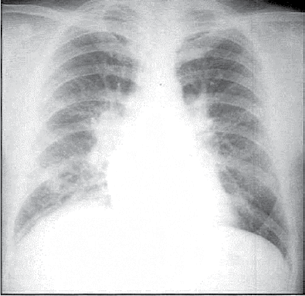

Paciente do sexo feminino, 39 anos, asmática, tem antecedente de valvopatia mitral reumática e estava assintomática até aproximadamente há 1 mês, quando passou a apresentar sintomas de dispneia em repouso e sensação de palpitação taquicárdica arrítmica. Procura atendimento médico por conta do cansaço intenso e o exame físico evidencia: taquidispneia em repouso, FC=pulso=120 bpm, PA = 120x80 mmHg, estertores crepitantes em 1/2 inferior de ambos os pulmões, associados a sibilos expiratórios, bulhas arrítmicas em 2 tempos, com sopro diastólico em foco mitral (ausculta dificultada pela alta frequência cardíaca). A radiografia de tórax e o eletrocardiograma dessa paciente encontram-se ilustrados a seguir.